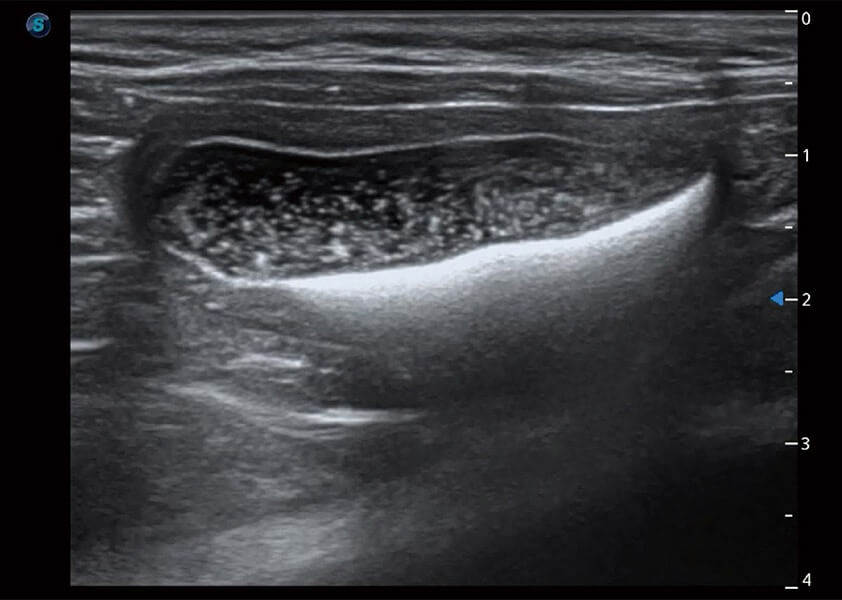

ProPet 60 作为一款高端台式动物超声设备,为动物医生的日常诊断提供了一系列贴合动物临床需求、解决临床实际问题的高级成像功能。凭借全系列高清探头,满足医生对腹部、心脏、生殖、浅表、肌骨等成像的所有需求,切实帮助您提升检查效率,提高诊断信心。

动物是人类最亲密的朋友和最值得信赖的伙伴。银河优越会也一直致力于探索动物专用的超声影像解决方案。 全新推出的ProPet系列,是银河优越会在动物超声影像智能化、专业化、精准化的一次跨越式革新。动物不能用言语来表述自己的不适,通过超声影像,ProPet系列搭建了动物医生与不同物种沟通的“桥梁”,为动物医生注入了“治愈之力”。